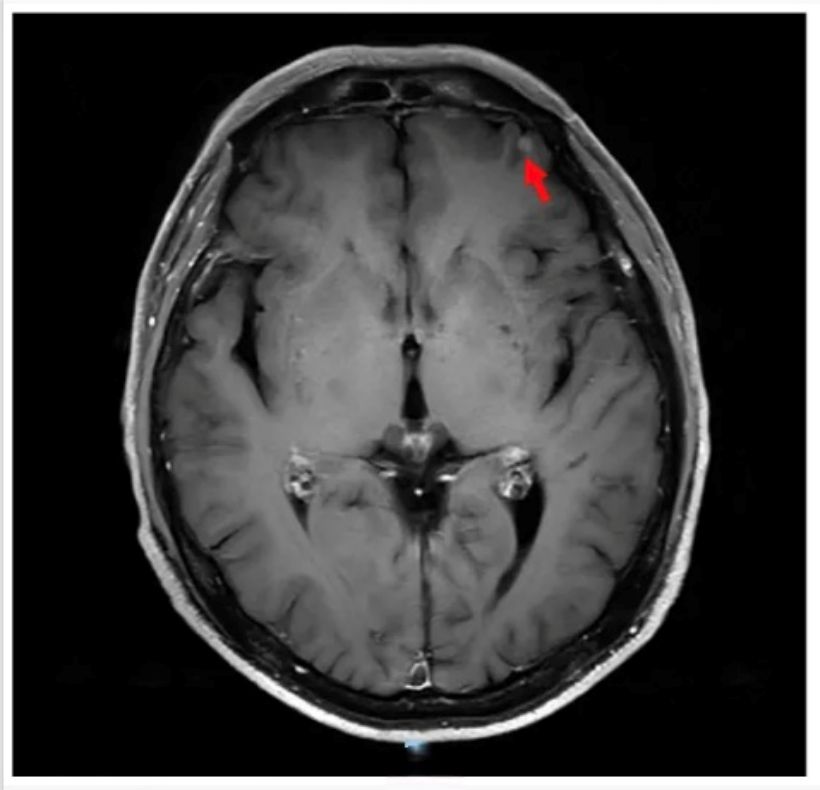

头颅增强MRI及DWI:左侧额叶见一结节样强化灶,考虑转移瘤(图2)。

图2 初诊时颅脑病灶(红色箭头指向病灶)[1]